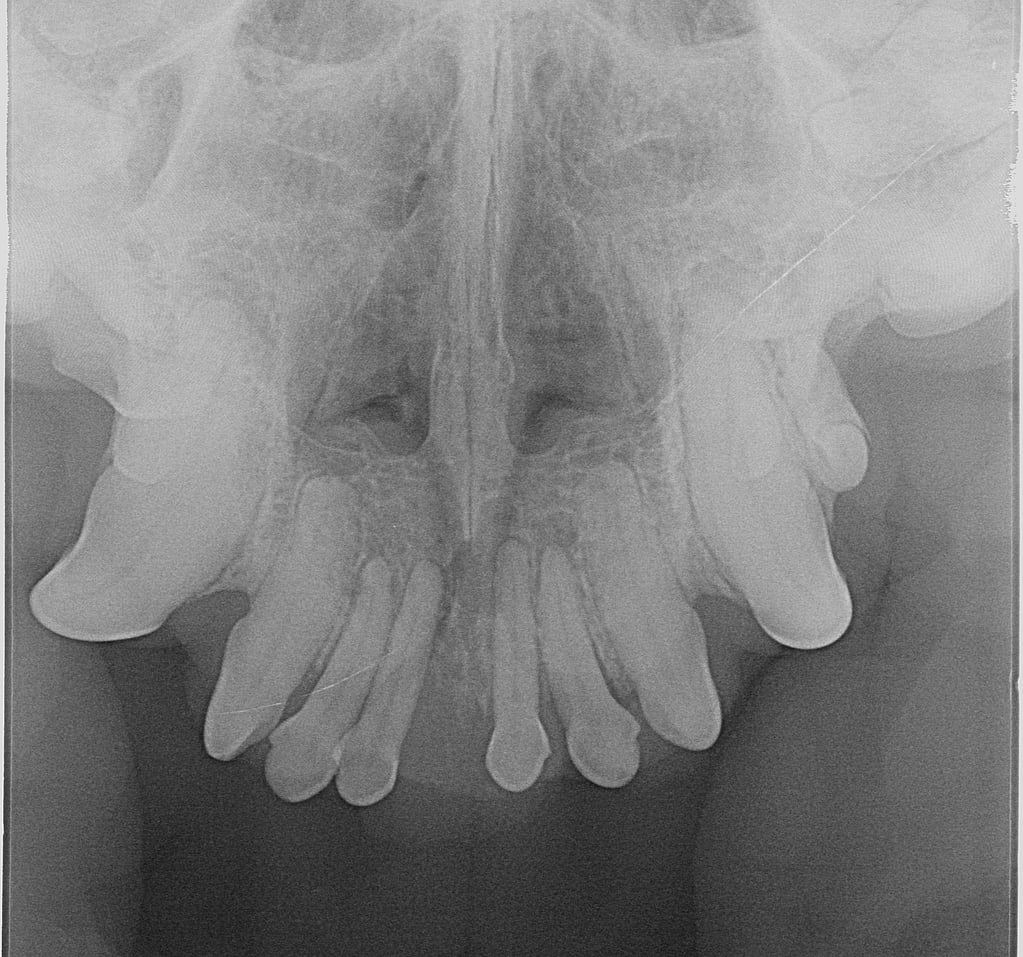

De gouden standaard voor beeldvorming bij tumoren in de mondholte is doorgaans CT, maar aangezien het om een ameloblastoom gaat en we weten dat het enkel lokaal invasief groeit, was dentale radiografie in dit geval voldoende.

We planden voor Rosa een premaxillectomie in, waarbij we een resectie doen van beide os incisivi inclusief alle omgevende weke delen/structuren (en block excisie).